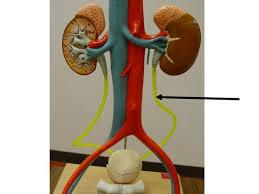

Afferent/efferent arteriole

Collecting duct

Descending/Ascending loop (of nephron)

Distal (convoluted) tubule

Glomerular capsule (=Bowman's capsule)

Glomerulus (=glomerular capillaries)

Gonadal (=testicular/ovarian) artery/vein

Juxtaglomerular apparatus

Medullary pyramids

Nephron

Peritubular capillaries

Proximal (convoluted) tubule

Renal artery/vein

Renal cortex

Renal medulla

Renal Pelvis

Ureter